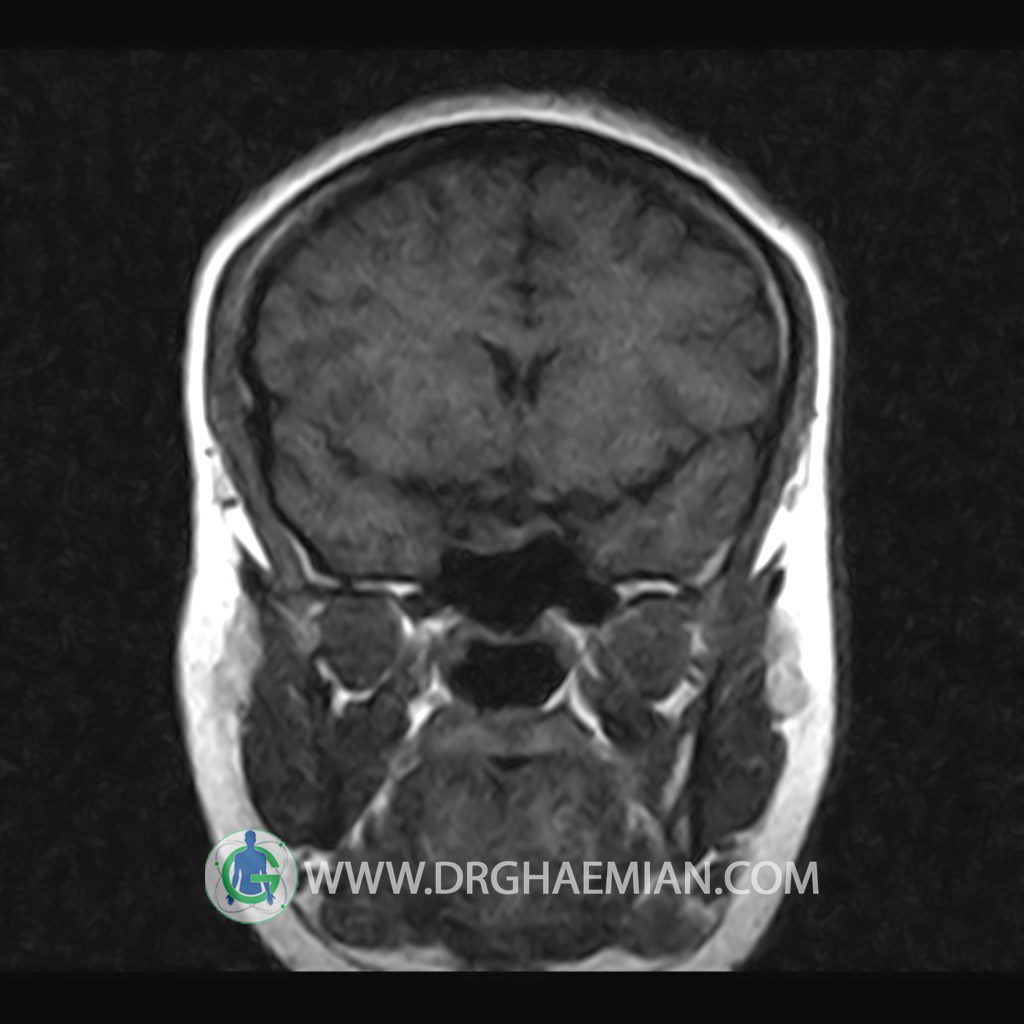

Technique: Axial , coronal T1 , Axial , coronal , sagittal T2 , Axial, coronal T1 post Gd & 64 dynamic thin coronal slices.

The infundibulum is centered and of normal size .

The optic chiasm and suprasellar spaces appear normal .

The cavernous sinus and imaged portions of the internal carotid artery and carotid siphon are unremarkable .

– Extension of suprasella cistern to sella with thin pituitary gland in floor of sella ( partial empty sella )

is seen